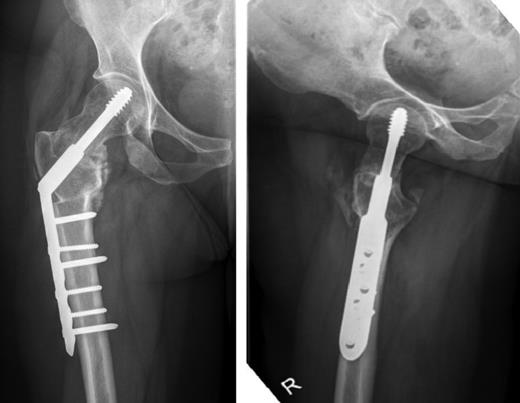

Pelvic and right hip radiograph's taken 5 months after the onset of symptoms demonstrating the fracture neck of femur.